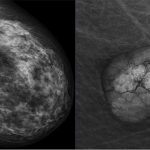

Vous vous demandez si la mammographie peut provoquer des douleurs ? La réponse est : cela dépend des personnes. Certaines ressentent une légère pression ou inconfort lorsque les seins sont compressés pour obtenir des images claires, tandis que d’autres peuvent trouver cela plus douloureux.